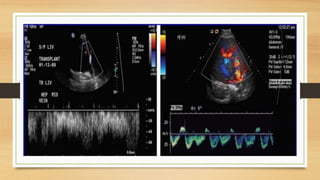

• #54 Transient dampening of the hepatic vein waveform in 51 yr old man after orthotopic liver transplantation . Duplex doppler image obtained 1 day after surgery shows the waveform of the middle hepatic vein . The spectrum is in the correct direction , posteriorly toward the IVC : however , the waveform is blunted the pt continued to do well clinically Duplex doppler image obtained 1 day later shows a normal waveform of the middle hepatic vein.